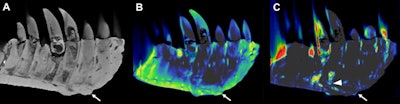

Otto's left lower jaw was successfully analyzed for bone disease using a clinical CT scanner with DECT. This technique allowed the researchers to scan the portion of the jaw called the left dentary, which in Otto's case measures a little over 2.5 ft (79.5 cm) long and 3 inches (81 mm) wide.

The left dentary of the jaw showed a diffuse thickening of nearly the entire dentary and a mass on its surface that extended to the root of one of the teeth. Inside the mass, DECT detected a significant accumulation of the element fluorine, which is associated with decreased bone density. The mass and fluorine accumulation findings supported a diagnosis of tumefactive osteomyelitis, an infection of the bone.

"The noninvasive density- and element-based material decomposition of fossilized bone revealed that fluorine could serve as an imaging biomarker for areas with decreased bone density, helping paleontologists to investigate fossils without the need to harm their integrity," the authors wrote.